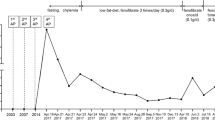

In the present study, a 28-year-old female Han Chinese with her first pregnancy during the third trimester was admitted to our emergency room and diagnosed with acute pancreatitis. Several days prior to this episode, lactescent levels were elevated in her serum however this was not noted. When admitted, blood tests revealed extremely high serum levels of HTG (TG 79 mmol/l, while normal ranges are 0.0-1.7 mmol/l). Following immediate cesarean section, she gave birth to a healthy baby girl and then was treated with dietary restriction and supportive treatment for 28 days, then discharged from the hospital.

Meanwhile, the 58-year-old mother was also admitted to our hospital with a diagnosis of acute pancreatitis. Including this hospitalization, she had two previous episodes of abdominal pain and was diagnosed with acute pancreatitis after intake of fatty food. The plasma levels of total triglyceride were 25.4 and 16.3 mmol/l, respectively at these episodes. The proband’ mother was married to her father at age 22 through a consanguineous marriage. Because these two patients presented with severe HTG and acute pancreatitis, they were strongly suggestive of an inherited condition.

Pedigree of the probands is shown in Figure 1. Mutational analyses of the LPL, APOC2, APOA5, LMF1, and GPIHBP1 genes showed that both patients had the same compound heterozygote of the LPL gene for a novel missense mutation (L279V) and a known missense mutation (A98T). One unrelated HTG patient was also found to be heterozygote of the p.(L279V) variant. The novel missense mutation L279V (p.L279V, rs371282890) at exon 6 is a CTG → GTG change in codon 279 of the LPL gene, leading to L → V amino acid substitution in the LPL protein (Figure 2). The known missense mutation of LPL A98T (p.A98T, rs145657341) is a GCC → ACC change in codon 98 of the LPL gene, leading to an A → T amino acid substitution (Figure 3). The father (I3) was found to be a carrier of L279V, while the uncle (I2), one aunt (I5) and the elder sister (II3) were carriers of A98T. I2, I5, I6 also have S447X mutations. There were no mutations found in APOC2, APOA5, GPIHBP1 or LMF1.

LPL mutations and biochemical features of these two patients and their family members are shown in Table 1. However, in cross species comparison, we found that L279 residue is very conserved across the species (Figure 4).